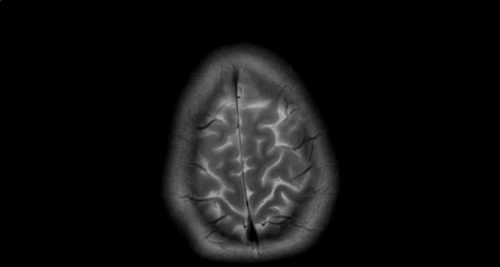

Κάθε τρία δευτερόλεπτα, κάποιος στον κόσμο εμφανίζει άνοια. Η νόσος Alzheimer (ΝΑ), αλλά και η άνοια γενικότερα, αποτελεί ένα δυσβάστακτο κοινωνικό πρόβλημα υγείας από την οποία πάσχουν 197.000 Έλληνες και σύμφωνα με τις προβλέψεις το 2050 ο αριθμός αυτός θα φτάσει στους 354.000. Στην Ελλάδα 400.000 περιθάλποντες παρέχουν καθημερινά φροντίδα στους ανθρώπους με άνοια, με πιο συχνή μορφή της τη νόσο Alzheimer, επωμιζόμενοι ένα τεράστιο πρακτικό, οικονομικό και ψυχικό φορτίο.